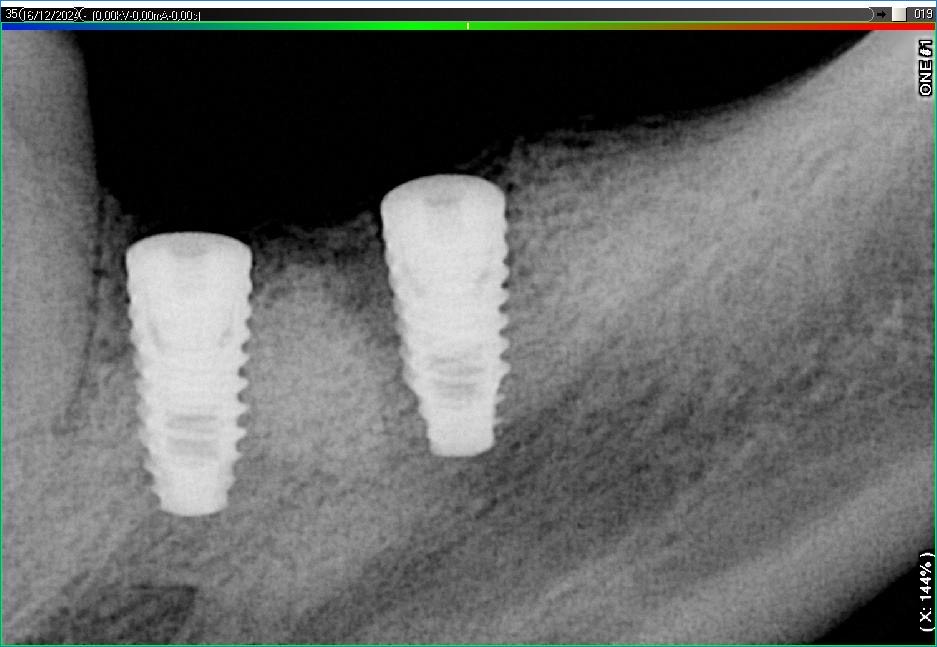

Імплантація